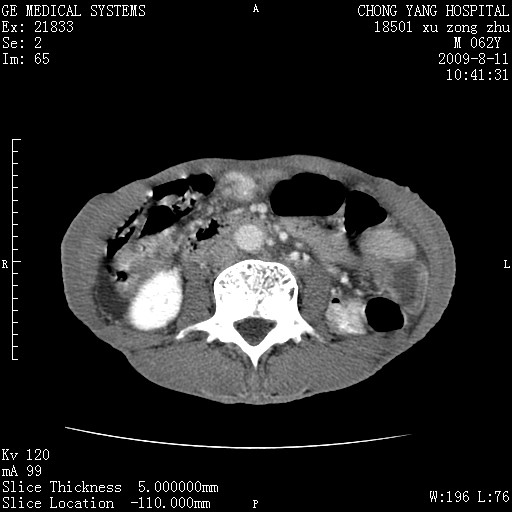

以下是引用杀毒软件在2009-8-11 16:35:00的发言:[br]肝内胆管扩张局限于左叶,胆管内有结石伴肝外胆管结石,胆管壁增厚呈弥漫性并发腹腔积液,胰腺边界模糊。[br][br]考虑---胆总管及肝内胆管结石继发胆管炎及胰腺炎,左肾下极囊肿,腹水。

以下是引用zjzjr在2009-8-11 17:35:00的发言:[br]肝内胆管扩张局限于左叶,胆管内有结石伴肝外胆管结石,胆管壁增厚呈弥漫性并发腹腔积液。[br][br]考虑---胆总管及肝内胆管结石继发胆管炎,左肾下极囊肿,腹水。